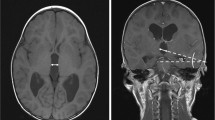

A three-year-old male with a history of premature birth with intraventricular hemorrhage, seizure disorder, and hydrocephalus treated with ventriculoatrial shunt (VAS) presented to the ED with increased seizure activity. The patient was admitted for observation and a CT scan was interpreted as stable. Two days later, a second CT scan was interpreted as possible, but not determinable, enlargement of the right frontal horn (Fig. 3). Given the stable neurological exam, the patient was subsequently discharged. He returned 6 weeks later with altered mental status, emesis, and lethargy. A shunt tap revealed slow proximal flow and a CT displayed an interval increase in size of the right frontal horn. Therefore, the patient underwent emergent proximal revision of the VAS without complications and was subsequently discharged.

Comparison of the CT scans in illustrative Case 3. In both images, the ventricular volume was calculated via the automated volumetric analysis. A This CT scan was taken upon initial presentation and the calculated ventricular volume is 66.0 mL. B This CT scan was taken two days after the initial presentation and the calculated ventricular volume is 73.5 mL. This corresponds to an increase of 11.3%

In all three of the presented cases, the automated volumetric analysis showed that the CSF ventricular volumes had increased since initial admission (41.7%, 43.8%, and 11.3%, respectively) (Table 1). This increase, however, was not definitively detected on routine interpretation by a neuroradiologist. Use of the novel algorithm would have detected these changes, therefore preventing the delay in the patients’ care.